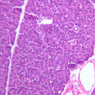

Sections through the wall of the gall bladder appear on slide B-33 (H&E [2.5x, 10x, 20x-labeled, 40x-labeled] [2.5x, 10x, 20x, 40x]). As you examine the epithelium, try to identify the striated border, which functions in absorbing water from the bile. Look for lymphocytes, capillaries and small mucous glands in the lamina propria; lymphocytes often appear to invade the epithelium itself. The gallbladder does not have a discernible submucosa; rather, a muscularis layer, consisting of smooth muscle and connective tissue underlies the mucosa. Some sections may permit identification of both a tunica adventitia, which binds the gallbladder to the liver, and a tunica serosa where the gallbladder faces the peritoneal cavity.

B33, Gallbladder, 2.5x (H&E) B33, Gallbladder, 10x (H&E) B33, Gallbladder, 20x Labeled (H&E) B33, Gallbladder, 40x Labeled (H&E) B33, Gallbladder, 2.5x (H&E) B33, Gallbladder, 10x (H&E) B33, Gallbladder, 20x (H&E) B33, Gallbladder, 40x (H&E)

4 Columnar Epithelium Ep H&E b33 gallbladder 40x labeled.jpgB33, Gallbladder, 40x

5 Striated Border SB H&E b33 gallbladder 40x labeled.jpgB33, Gallbladder, 40x

6 Lymphocytes L H&E b33 gallbladder 40x labeled.jpgB33, Gallbladder, 40x